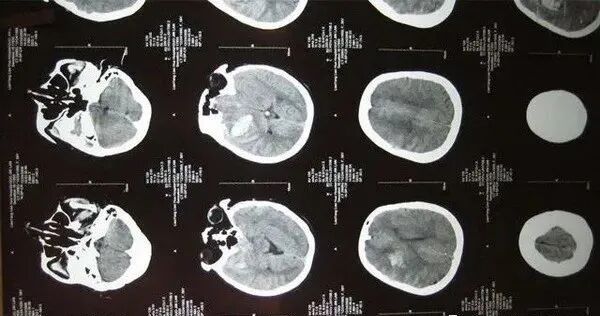

案例丨干细胞治疗脑出血后遗症,康复新希望

出血是非外伤性脑实质内血管破裂引起的出血,占全部脑卒中的20%~30%,急性期病死率为30%~40%。脑出血患者一般都会留下后遗症,而后遗症的康复是一个漫长的过程。近年来,干细胞疗法的发展给神经系统性疾病带来了希望,也让临床控制脑出血后遗症成为了可能。

脑出血(intracerebral hemorrhage,ICH)是出血性脑卒中最常见的亚型,占急性脑血管疾病(中风)的20%-30%,ICH 在急性期死亡率为30%-40%。

人类一旦发生脑出血、脑梗死等疾病后,患者身体内上下行神经传导通路部分或全部离断,引起神经功能缺失,损伤的神经功能难以恢复,多遗留严重的后遗症,给生活带来了严重困扰。